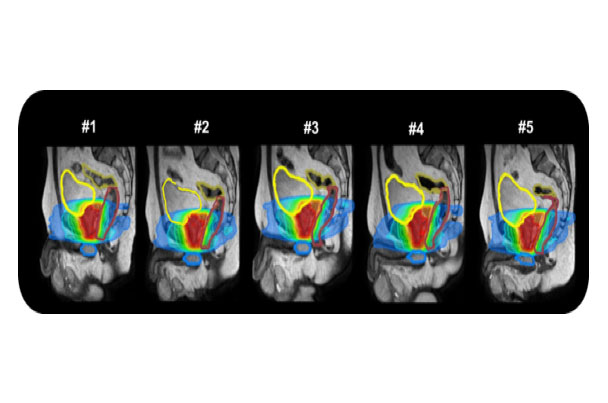

随着生活水平的提高,前列腺癌大发病逐渐上升,剂量学研究和初步的临床实践已经显示调强是当今放疗前列腺癌的最好照射技术,有广泛的应用前景,磁共振引导技术可以更好的对前列腺组织进行分辨,可以进行功能保留行治疗及肿瘤消融治疗,同时磁共振功能成像技术也为治疗疗效提供生物学依据。

利用磁共振引导的调强治疗技术能够对更加精确的对肿瘤及周围淋巴结进行精确的放射治疗。

磁共振实时成像可动态监测由于膀胱充盈不同或肠道蠕动带来的靶区位置形状改变,并进行自适应计划调整,更好的提高靶区剂量覆盖。